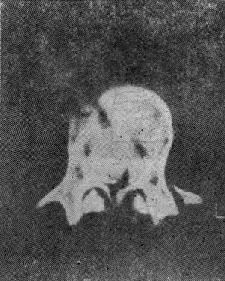

图73-2 脊柱旋转损伤 (三)爆裂型骨折 是由沿身体纵轴作用的暴力造成的骨折。椎间盘被压入椎体终板,进入松质骨内致伤。椎体由中央“爆炸”样裂开,将骨折片推向四方,有椎体后缘骨折,且有骨折片突入椎管内(图73-3)。椎弓根之间的距离裂开、增宽。常合并后方椎板的纵行骨折,前方椎体裂开越大,椎板骨折就越明显(图73-4)。有时仅有椎板内板骨折,要CT扫描才能发现。爆裂型骨折又可分成五种:①同时有上、下终板损伤,伴有椎体后缘骨折片突入椎管,压迫脊髓,产生神经系统症状;②椎体上半部骨折,椎体后方压缩,有骨折片旋转进入椎管内,此型最多见;③下方椎体终板损伤;④爆炸型合并有旋转骨折,除有爆裂型骨折特征外,还可见旋转棘突偏歪一侧;⑤爆炸型骨折合并侧方压缩骨折,骨折线斜行过椎体,椎弓根距离增宽,椎体两侧高度不一样,常伴有多发横突骨折,此型最不稳定。

图73-3 爆裂型骨折

图73-4 椎板纵行骨折 爆炸型骨折的主要特点为:椎弓根间距增宽,椎体后部压缩,高度变小,及椎体横径增宽。几乎所有爆裂型骨折都具有神经系统症状。 (四)剪力骨折 又称切片状骨折(slice fracture)。常为屈曲旋转暴力引起,脊椎前、后方所有韧带均撕裂,可伴有一侧或两侧小关节、横突及椎弓根的骨折,但椎体骨质破坏不明显,椎体高度不变。但旋转剪力可将下一个椎体上缘撕脱小片骨质,就像刀切下一薄片一样(图73-5)。由于所有结构几乎完全横断,骨折高度不稳定,病人常常合并完全截瘫。X线片可见“切片”状骨折片和椎间隙增宽的特点。 (五)椎体后部骨折 又称座带骨折(seat belt fracture)。由Chance于1948年首先描述此骨折,故文献又常称Chance骨折,为一种屈曲拉伸骨折。典型的损伤机制为汽车座带束于患者腰腹部,当高速行驶的汽车突然减速或撞车时,座带支点以上的躯干屈曲,前冲力还同时产生一个向前拉伸的力量(图73-6)。将椎体由后方向前撕裂,骨折线横过椎体、椎弓根和椎板,椎体后部的韧带完全撕裂(图73-7)。有时前纵韧带亦可撕裂,常合并有神经系统的症状。